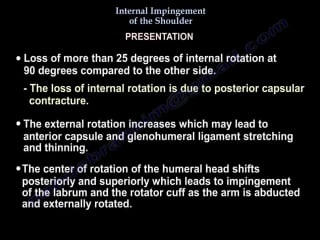

Internal impingement of the shoulder everything you need to know dr nabil eb